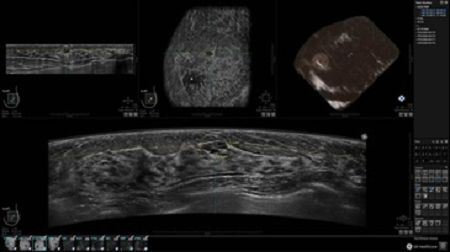

GE INVENIA ABUS – это современный УЗИ аппарат, который создан для точной и эффективной диагностики сканирования с высокой плотностью молочных желез. Выявляемость патологий раковых и предраковых стадий заболевания составляет 55%, что в конечном счете позволяет ставить врачу точные и своевременные диагнозы. Традиционные методы использования маммографии не показывают такой выявляемости, ограничиваясь лишь 3-38%.

УЗИ-аппарат GE INVENIA ABUS позволяет проводить максимально операторонезависимые процедуры, что значительно снижает риск неправильной постановки диагноза и сопутствующие издержки на обработку информации. Система готовит отчет в течение 3-х минут после сканирования, это безусловное преимущество по сравнению с обычным УЗИ сканером.

• Получение объемных 3D изображений с возможностью покадрового просмотра

• Получение изображений в поперечной плоскости (в реальном времени) и в коронарной плоскости (статическая, для указания нахождения соска)

• Отображение объемных 3D ультразвуковых изображений, которые состоят из традиционных поперечных и воссозданных коронарных и сагиттальных проекций

• Стандартизованная ориентация изображения: «толстый срез» в коронарной плоскости; поперечная; сагиттальная плоскость; радиальный и антирадиальный поворот изображения; просмотр исключительно области интереса